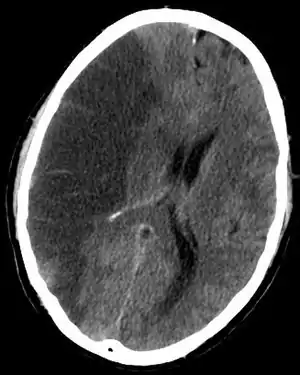

CT scan slice of the brain showing a right-hemispheric cerebral infarct (left side of image).